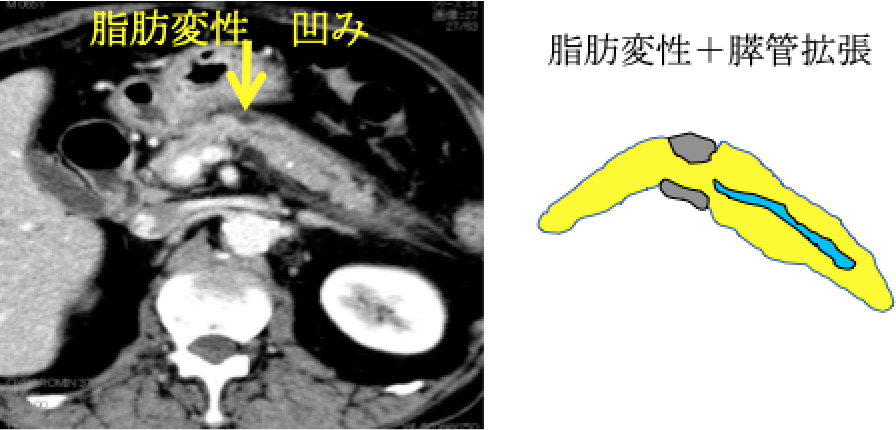

膵臓がんはすい管(消化液〈=すい液〉の通り道)から発生する膵管がんと言われています。 膵臓がんを発症すると、すい管が狭くなり、膵液が停滞します。その際に、主膵管拡張・膵のう胞(分枝膵管拡張)・脂肪変性(膵臓の凹みや痩せ)・腫れといった変化を引き起こします(膵臓がんの間接所見)。これにともなって、膵臓の炎症を起こしたり(みぞおちの痛み)、膵臓のはたらきが低下します(糖尿病の発症や悪化、味覚の変化、下痢など)。顕微鏡レベルの膵臓がん(上皮内がん)でも上記の間接所見や症状を伴うものがあることがわかってきました。膵臓がんが発生してから転移するまで約7年かかると言われております。この間に膵臓の形や膵管の変化をとらえることで早期の膵癌が発見できる可能性があります。

③ 膵脂肪変性(凹み)、膵管拡張